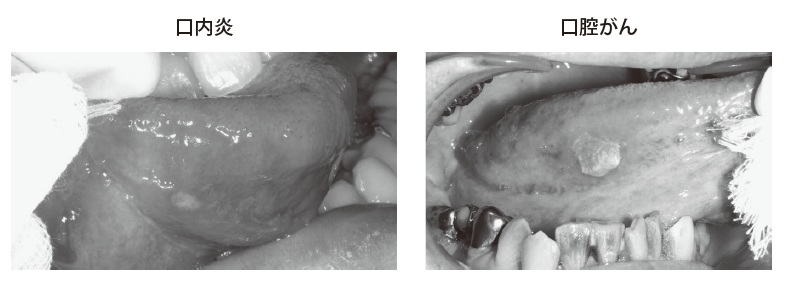

全身疾患の原因ではありませんが、口腔内は扁平上皮がんができます。舌であれば舌扁平上皮がん。局所の原因ではありますが、潰瘍型の扁平上皮がんもあるので、見落としてはならないと思います。見た目としては、一般的なアフタ性口内炎よりも潰瘍の周囲が膨隆していたり、周囲が硬結していたり、そういったところでの違いがあるかと思います。

あとは病悩期間ですね。口内炎は一般的には2週間以内には治っているはずなのですが、2週間以上も続くのであれば、悪性の変化も考えなければなりません。患者さんの問診で、病悩期間を確認することも非常に重要ではないかなと考えます。

非常に大切だと思います。一般的な口内炎、アフタ性の口内炎であれば硬いということはまずありませんので、触ってみて硬い、膨隆している、そして易出血性であれば、扁平上皮がんの可能性があると思っていただいていいと思います。